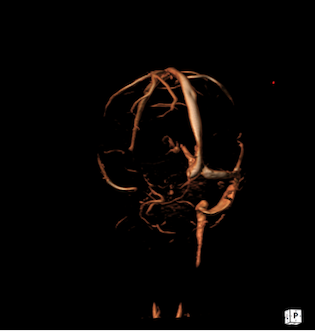

In considerazione della storia clinica, i bambini venivano sottoposti a RM che evidenziava in entrambi i casi un quadro di trombosi venosa cerebrale, con estensione nel primo caso al seno trasverso, sigmoideo e bulbo della giugulare destro, in associazione alla presenza di segni di flogosi a carico delle cellette mastoidee (Figura 1), mentre nel secondo caso trombosi subacuta con coinvolgimento di seno trasverso, sigmoideo, bulbo, tratto craniale della giugulare interna e sospetto iniziale impegno della vena di Labbé a sinistra, senza flogosi mastoidea (Figura 2).